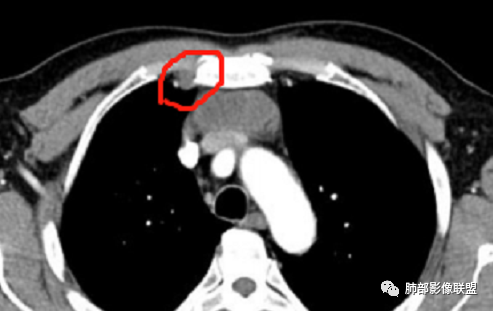

南边:

老年男性,胸背痛,定位前纵隔,囊实性占位。

似有小点状钙化(说似有的原因是横轴位没找到)。

这里边界似乎不太清楚

有分叶。

质地偏软,有点见缝就钻。

紧贴血管,侵犯不明显。

多发小淋巴结。

囊变坏死区分界不清。

内乳淋巴结

我记得黄勇老师的课件提到:内乳淋巴结、钙化有价值。

中老年男性,前纵隔占位,基本居中,向两侧生长;边缘膨隆分叶,部分边界不清,增强不均匀轻中度强化,坏死区边界不清;周围多发增大淋巴结,考虑恶性。主要在胸腺癌、胸腺瘤、淋巴瘤之间鉴别。病灶偏软,有钻缝样生长,这些征象偏向于淋巴瘤。但此例老年患者,病灶内有点状钙化,缺乏结节堆砌感,倾向胸腺癌诊断。